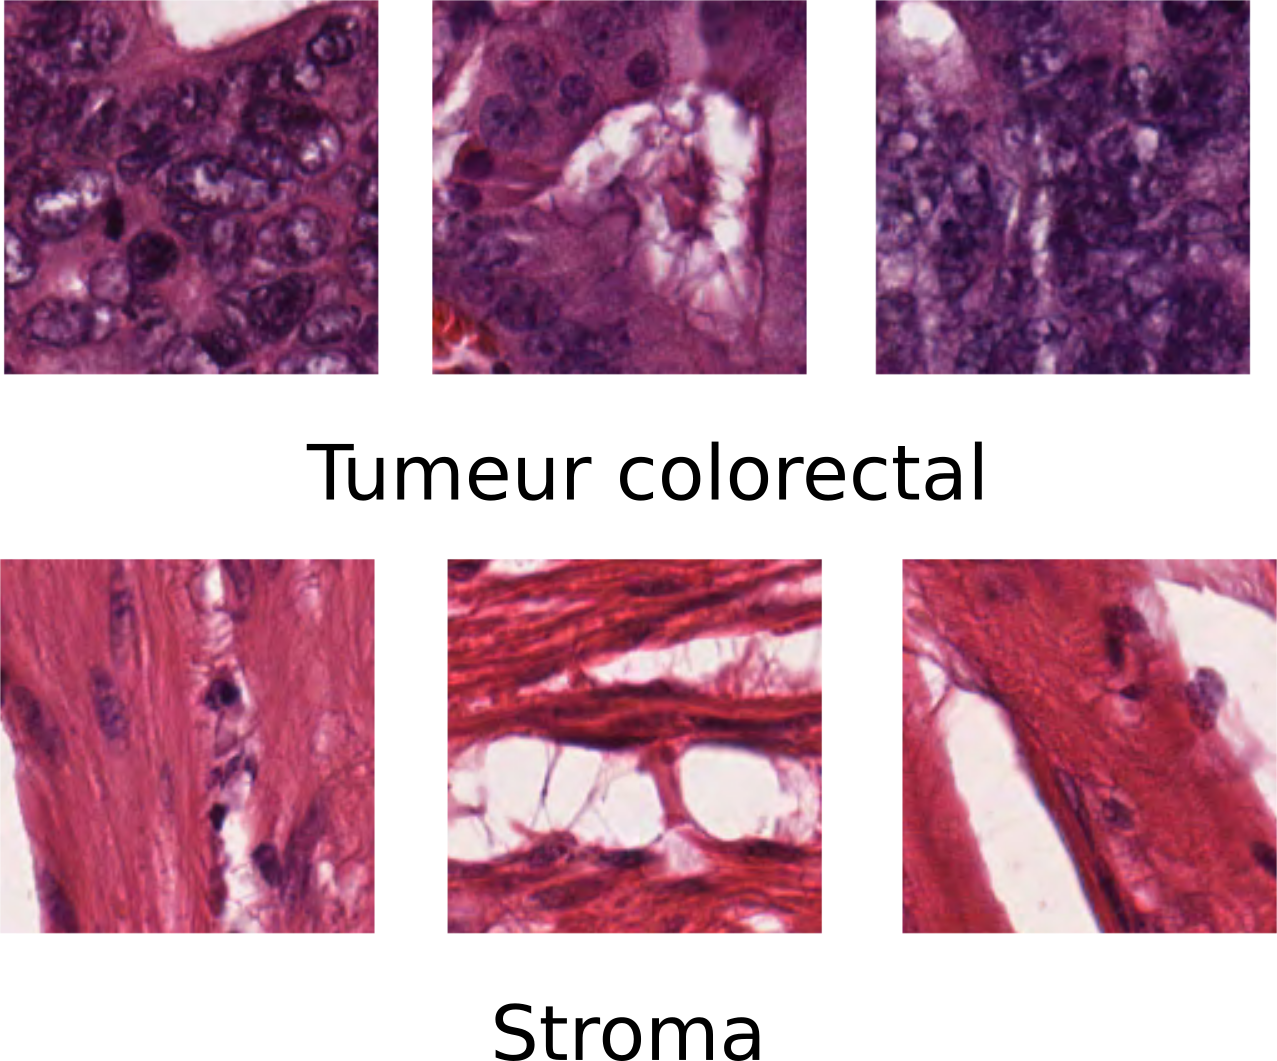

Pour diagnostiquer le cancer, les médecins utilisent l’analyse histopathologique, celle-ci consiste à prélever un tissu malade sur le patient (biopsie) et à l’observé au microscope afin de détecter et de quantifier les cellules cancéreuses. Il est très important lors des stades précoces du cancer de savoir distinguer les cellules cancéreuses des cellules saines.

Lors de l’examen de l’échantillon sous le microscope, le pathologiste cherchera notamment la présence d'anomalies dans la structure des cellules où des changements dans la distribution de ces dernières. Ce diagnostic est très subjectif, car pour l’effectuer le médecin se repose principalement sur son expérience et donc cela mène à une énorme variabilité de l’analyse d’un pathologiste à l'autre. C’est pourquoi afin de normaliser ce processus d’analyse, il est important d’automatiser le diagnostic du cancer à l’aide d’outils logiciels capables de réaliser des mesures quantitatives permettant ainsi au médecin d’avoir un jugement objectif de la situation du patient.

La segmentation est l’étape durant laquelle les objets d’intérêt sont détectés puis extraits de l’image. Dans le cas ci-dessus la segmentation a simplement découpé l’image du tissue qui à l’origine mesurait 5000*5000 pixels a été découpé en sous-image de 50 x 50 pixels. Le but de cette segmentation est probablement de savoir avec précision jusqu’ou le tissu a été infecté par la tumeur.

Les objets précédemment extraits de l’image sont analysés afin d’en retirer des mesures pertinentes descriptives du problème à traiter. Dans le problème ci-dessus, les informations qui seront extraites seront des informations de texture et de couleurs. Car l’on peut remarquer que la texture et la couleur de l’échantillon changent selon que la zone traitée soit infectée ou pas.